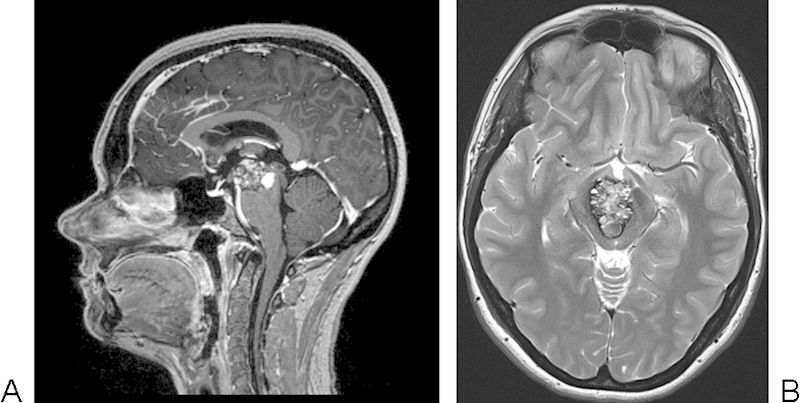

一位34歲的女性,既往無合并癥病史,因雙眼失明而聯(lián)系了她的全科醫(yī)生。她被咨詢給眼科醫(yī)生并開了光學(xué)鏡片。由于持續(xù)的復(fù)視和無法集中注意力,一年后她被咨詢?yōu)槟X部磁共振成像(MRI)掃描。磁共振成像顯示中腦位于腳間池后方。由于其規(guī)模小、位置雄辯,較初沒有采取任何措施。門診部的常規(guī)對(duì)照顯示,直到2012年夏季中期,癥狀沒有進(jìn)展或腫瘤體積增大。然后她出現(xiàn)頭暈,雙眼視力惡化,失衡。新的核磁共振顯示MeCM的進(jìn)展(圖1A,B),她被轉(zhuǎn)介到我們的神經(jīng)外科。神經(jīng)系統(tǒng)檢查顯示復(fù)視,核間眼肌麻痹伴隱動(dòng)神經(jīng)明顯損害,右眼瞳孔半擴(kuò)張,瞳孔光反射緩慢,調(diào)節(jié)障礙。沒有共濟(jì)失調(diào)或其他步態(tài)障礙的跡象。然而,她繼續(xù)惡化,癥狀惡化,1個(gè)月后出現(xiàn)全身性頭痛。她因此接受了手術(shù)。

圖1:腦干海綿狀血管瘤位于中腦的腳間池后方并延伸至三腦室。(A) T1加權(quán)MRI矢狀面與對(duì)比劑。(B) 無造影劑的軸位T2加權(quán)MRI。